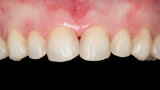

Fig. 1: Initial clinical situation.

Fig. 2: Initial clinical situation.

Fig. 3: Initial clinical situation.

Fig. 4: Initial clinical situation.